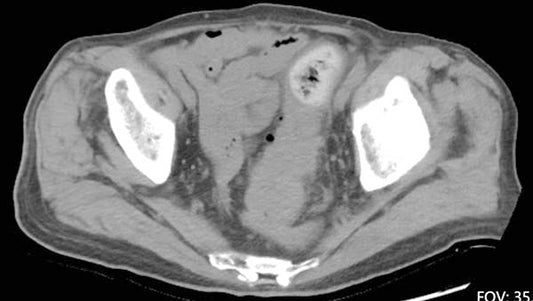

The expert team at Fuwai Hospital (Beijing) has successfully pioneered Renal Denervation (RDN) for Refractory Hypertension (RH). By utilizing radiofrequency energy to suppress hyperactive sympathetic drive, this procedure offers a...